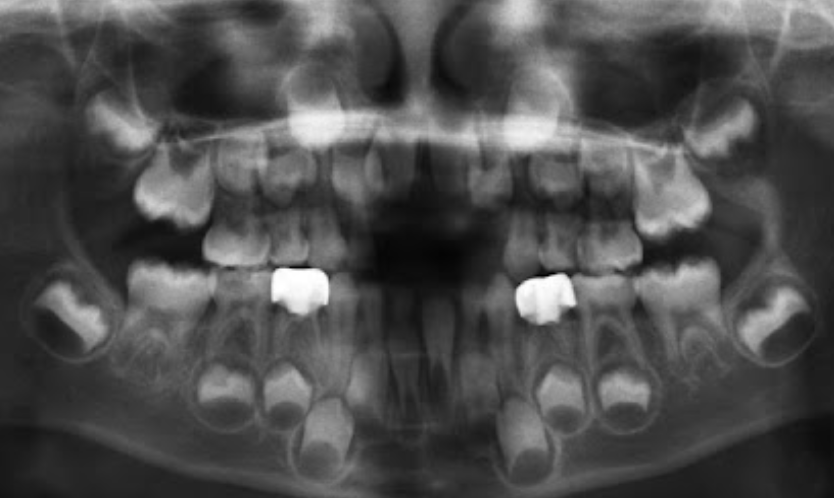

1.Ad. LOWER central incisors present? Yes. definitely 6-7 or older

1. Ad. UPPER CI present? Yes def. 7-8 y.o

3.Ad. Upper LAT incisor present (baby sheds 7-8)? NO so still under 7-8

Conc: pt is under 7